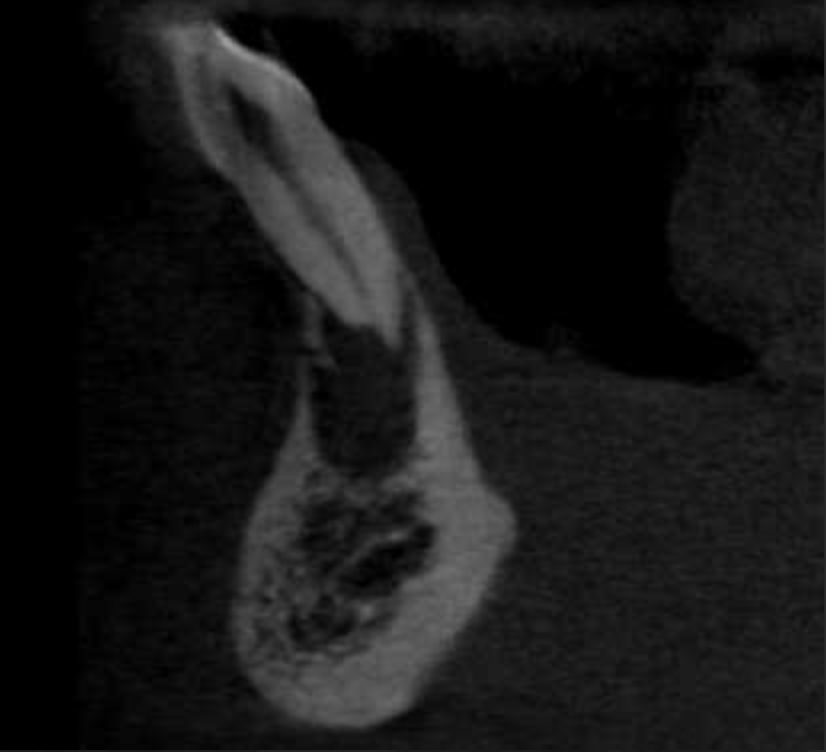

Fistula, dent in dente